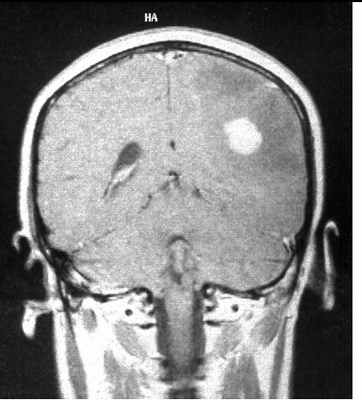

МРТ головного мозга. Множественная анапластическая астроцитома (стрелки). Сагиттальная Т1-зависимая МРТ с контрастированием.